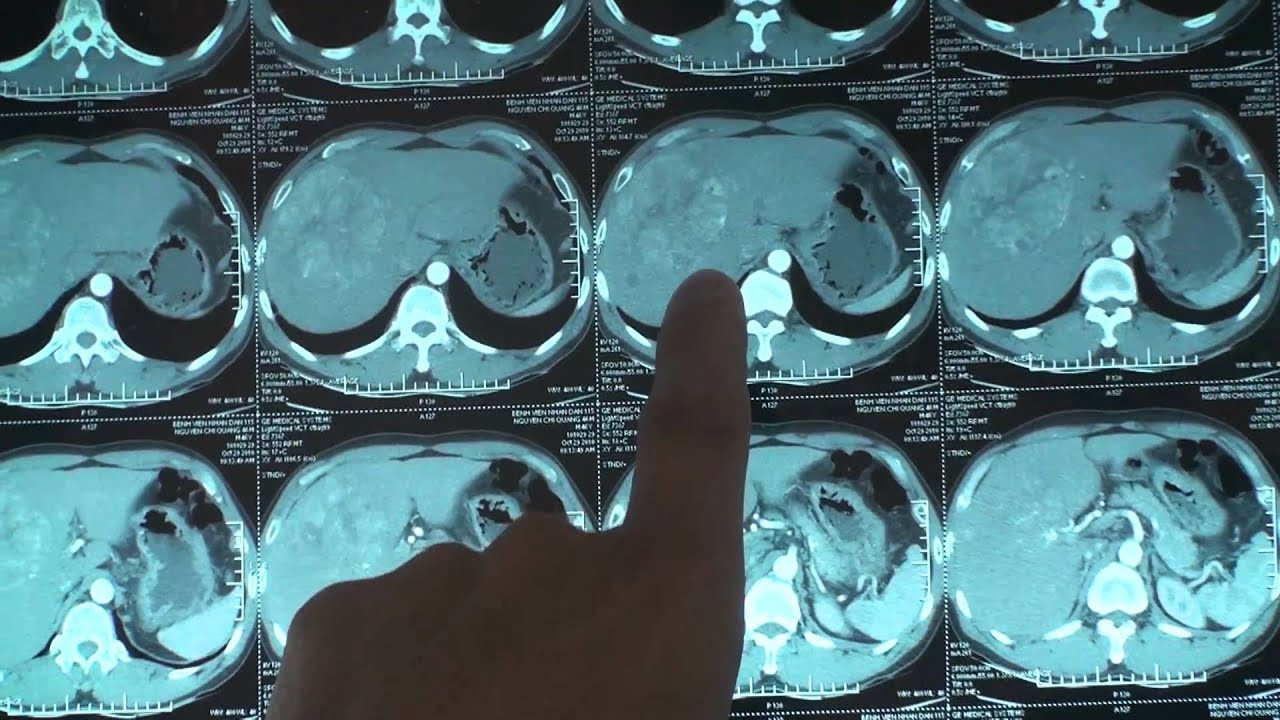

Bệnh nhân N.M. (19 tuổi, trú tại Bắc Ninh) đến Bệnh viện Bạch Mai (Hà Nội) khám trong tình trạng mệt mỏi, chán ăn, da và mắt vàng rõ. Qua thăm khám lâm sàng, các bác sĩ nghi ngờ M. tổn thương gan và chỉ định siêu âm ổ bụng. Kết quả cho thấy gan có khối u bất thường. Sau đó, bệnh nhân được chụp MSCT ổ bụng có tiêm thuốc cản quang, phát hiện một khối u lớn trong nhu mô gan với kích thước lên tới 9x6cm.

Các xét nghiệm chuyên sâu cho thấy bệnh nhân dương tính với virus viêm gan B. Trước tình trạng tổn thương gan nghiêm trọng, các bác sĩ chẩn đoán bệnh nhân mắc ung thư gan và tư vấn phương án điều trị phù hợp.